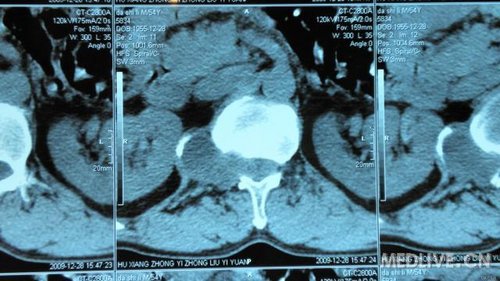

串者因腰椎间盘突出入院治疗,但询问病史查体时发现患者近1月来出现右腹股沟处麻木,局部感觉减退。做MRI等检查发现L1、2处椎管肿瘤。准备行手术治疗,但患者经济困难。各位专家指点一下选什么手术入路对脊柱稳定性影响比较小,尽量不上内固守。

还有CT片